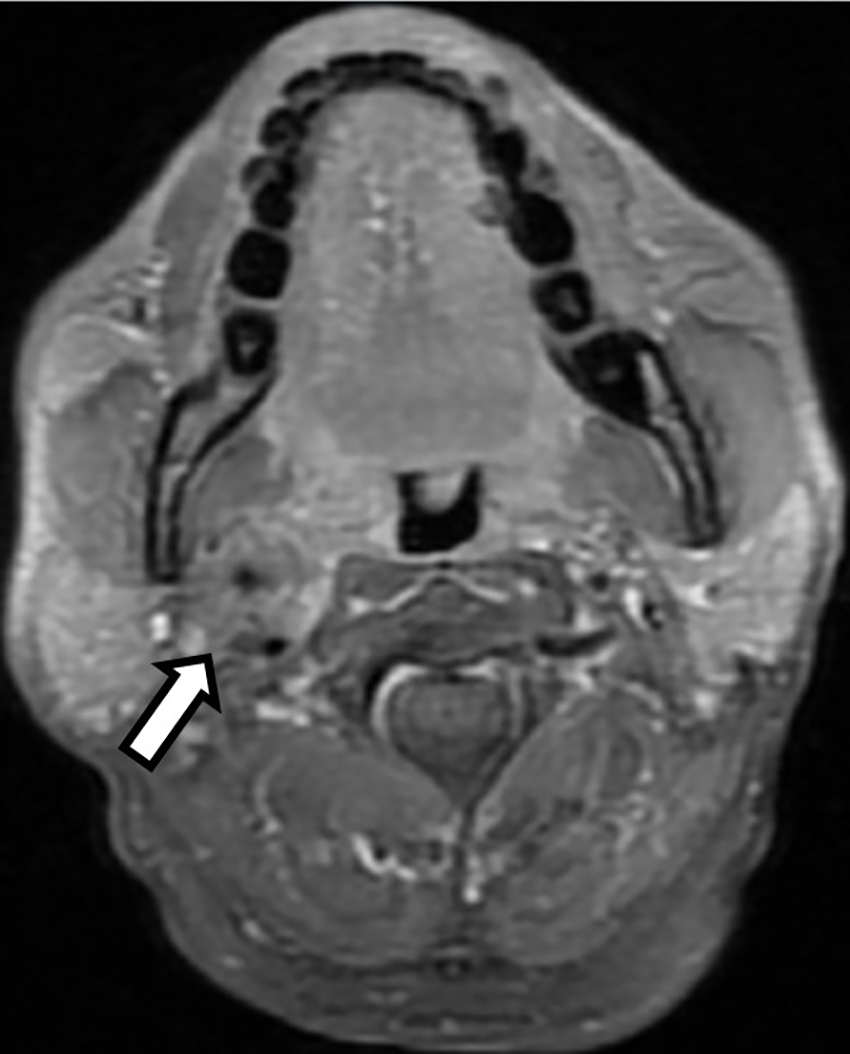

A 64-year-old male presented to the oncology department of our hospital with pulsatile right neck mass for one year. It was associated with dizziness and near-syncope. He was quite healthy without past medical history. On physical examination, a pulsatile mass about 2 cm was palpable over right submandibular region. Carotid bruit was not audible while auscultation and the mass were invisible upon oral cavity inspection. The absence of symptoms of hoarseness or dysphagia indicated no pressure on the larynx or pharynx. Vocal cord paralysis was also excluded after laryngoscopy examination. Magnetic resonance image (MRI) of the head and neck revealed a 2.6-centimeter soft tissue mass occupying the right carotid space and the right parapharyngeal space at the level of carotid bifurcation (Figure 1). The mass encased and constricted both the external and internal carotid arteries. The differential diagnosis included early nasopharyngeal mucosal lesion with submucosal spreading, metastatic lymphadenopathy, and neurogenic tumor. Contralateral carotid body was free of disease and there were no regional lymphadenopathy or distant metastases on computed tomography as well as whole-body bone scan.

Figure 1

T1-weighted head and neck magnetic resonance image (MRI) with fat saturation revealed a 2.6 centimeter enhancing soft tissue lesion occupying the right carotid space and the right parapharyngeal space at the level of carotid bifurcation with right internal and external carotid artery encasement (Open arrow).